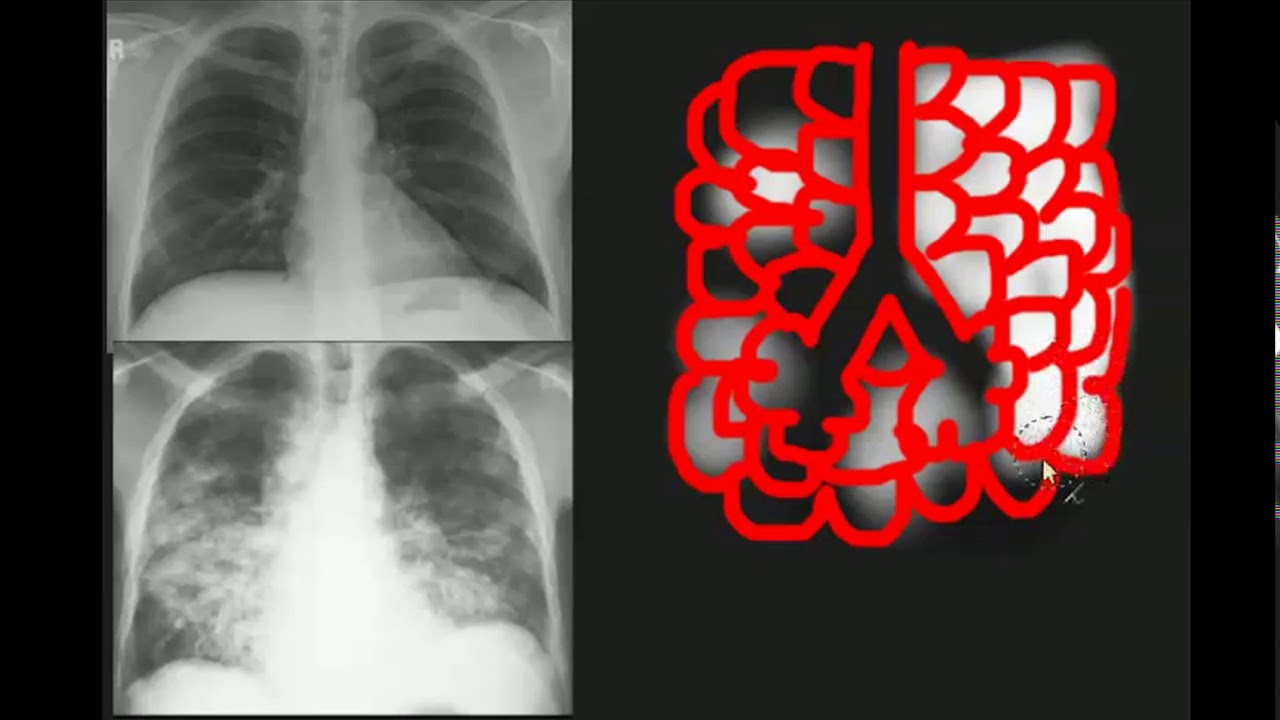

sem mais delongas bora falar sobre a complacência da parede torácica os vídeos anteriores a gente falou bastante sobre a complacência pulmonar a qual é determinada pela elastância Isto é pela retração elástica dos pulmões mas assim como os pulmões a parede torácica também é elástica e isso pode ser percebido no pneumotórax Pois Enquanto pulmão se retrai causando o seu colapso a parede torácica se expande e isso significa que o pulmão é tracionado para dentro e a parede que é tracionada para fora durante o repouso Isto é ao final de uma expiração quando não estamos nem expirando

pulmonar e da parede torácica seja importante é preciso saber que o pulmão e a parede torácica funcionam como uma unidade e quando ambos se separam como acontece no pneumotórax por exemplo a ventilação pulmonar não ocorre porém precisamos sempre lembrar que a complacência do sistema pode ser alterada tanto por alteração da pulmonar como também por alteração da complacência da parede torácica como acontece na obesidade por exemplo daí a importância de se estudar a complacência dessas estruturas de forma individual bom Espero que esse vídeo tenha te ajudado de alguma forma e se você gostou do vídeo comenta